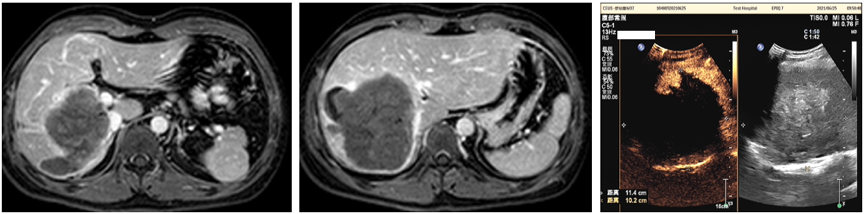

2021年7月31日磁共振增强扫描,与2021年6月13日前片比较:肝S6-8肿块呈术后坏死改变,未见明确活癌灶,肝左叶代偿性增大。门脉右支内充盈缺损,考虑栓子形成,大致同前。右侧心膈角及肝门区见小淋巴结影,建议复查(图5)。

图5.2021年7月31日复查MR